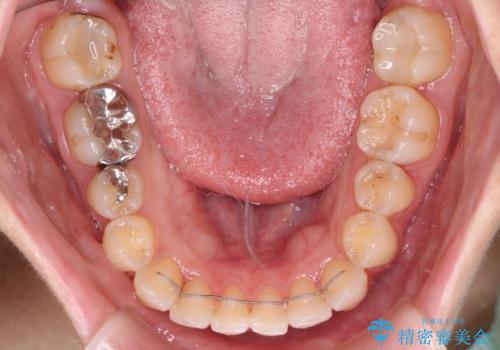

- 前歯のデコボコを気にして来院された患者様です。

主に下顎歯列全体の後方移動とIPR(歯と歯の間を削る)によってデコボコが解消するように設計し、インビザラインにより治療を行うこととしました。

舌突出癖がある方ですと、叢生が解消すると同時に前方に拡大されてしまいますが、ゴムかけをしっかりと行ってくださったこともあり、スッキリとした仕上がりとなりました。